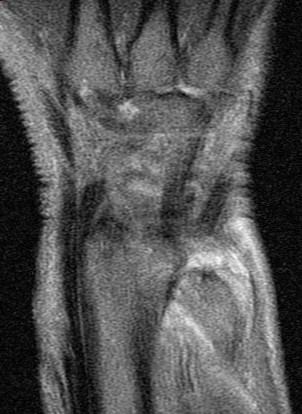

Ulnar impingement syndrome